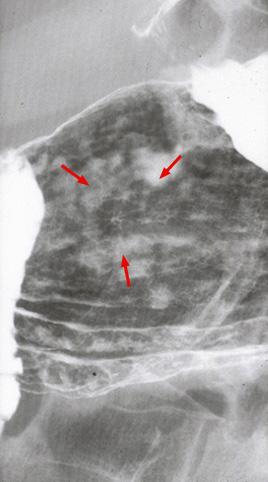

Criteria of Hist.ClassificationMalignant epithelial tumor/Adenocarcinoma

LocationStomach/Body

Technique, MethodX-ray

Macroscopic TypesType 0/IIc (IIc) Superficial depressed type

Size1 - 9

Depth of Tumor Invasionmucosa